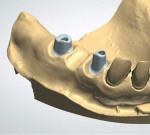

Upper provisional restorations were fabricated from the diagnostic wax-up using a PVS matrix, with the posteriors retained on temporary abutments.9 The posterior crowns would be fabricated from layered zirconia for strength and opacity to block out the underlying metal abutments. The anterior crowns would be lithium disilicate due to the enhanced esthetic quality of that material. The visual length of the maxillary implant teeth was determined in the laboratory first (Figure 6 through Figure 10), with the clinical gingival management done at the seat appointment. Slight occlusal adjustment was needed on the mandibular arch to create bilateral equal posterior contact in occlusion. The patient returned the following day for impressions of the provisional restorations and photographs, and to obtain centric occlusion records. The record was taken by creating a small direct composite deprogrammer on the palatal surface of teeth Nos. 8 and 9, opening the bite 0.5 mm.10 The maxillary posterior provisional restorations were removed, tall healing caps were placed in the implants, and a bite registration was taken. Healing caps were removed and sent with the case to the laboratory for mounting.

From the diagnostic mounting, a blueprint of the final restorations was generated to guide the patient's treatment decisions and create matrices for the provisional restorations. In the dental laboratory, a soft-tissue model was poured to replicate the patient's clinical situation. Before designing the custom milled abutments, and with the diagnostic cast as a reference, the dental technician was able to alter the soft-tissue coronal to the implant fixture (Figure 6 through Figure 8). Preparing the tissue prior to 3D scanning for the abutment design made it possible to control the emergence and create more visible tooth structure (Figure 9 and Figure 10), harmonizing with the gingival position of the anterior teeth and addressing the patient's concern with the visible length of the restorations.11